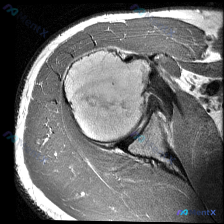

肩部MRI-T1像显示盂唇形态正常,但临床怀疑盂唇病变?这个矛盾点怎么解?

看到一个肩部病例,患者被怀疑有盂唇病变,但当前提供的T1加权轴位MRI显示盂唇形态完整、信号正常,无明显撕裂或异常。这个矛盾点比较值得讨论,大家怎么看?

- 骨骼结构:肱骨头形态圆滑,骨髓信号均匀中高,无骨折或骨质破坏;关节盂边缘清晰,骨质结构完整。

- 关节与盂唇:关节间隙对合良好,盂唇显示为三角形低信号结构,附着于关节盂边缘,形态完整,未见撕裂、分离或异常信号。

- 肌腱与肌肉:肩胛下肌腱走行正常,信号均匀;冈下肌/小圆肌形态饱满,无明显萎缩。

但影像分析也提到了T1序列的局限性,对水分(炎症、水肿、部分撕裂积液)敏感性较低,必须结合T2压脂或PD压脂序列才能更全面评估。